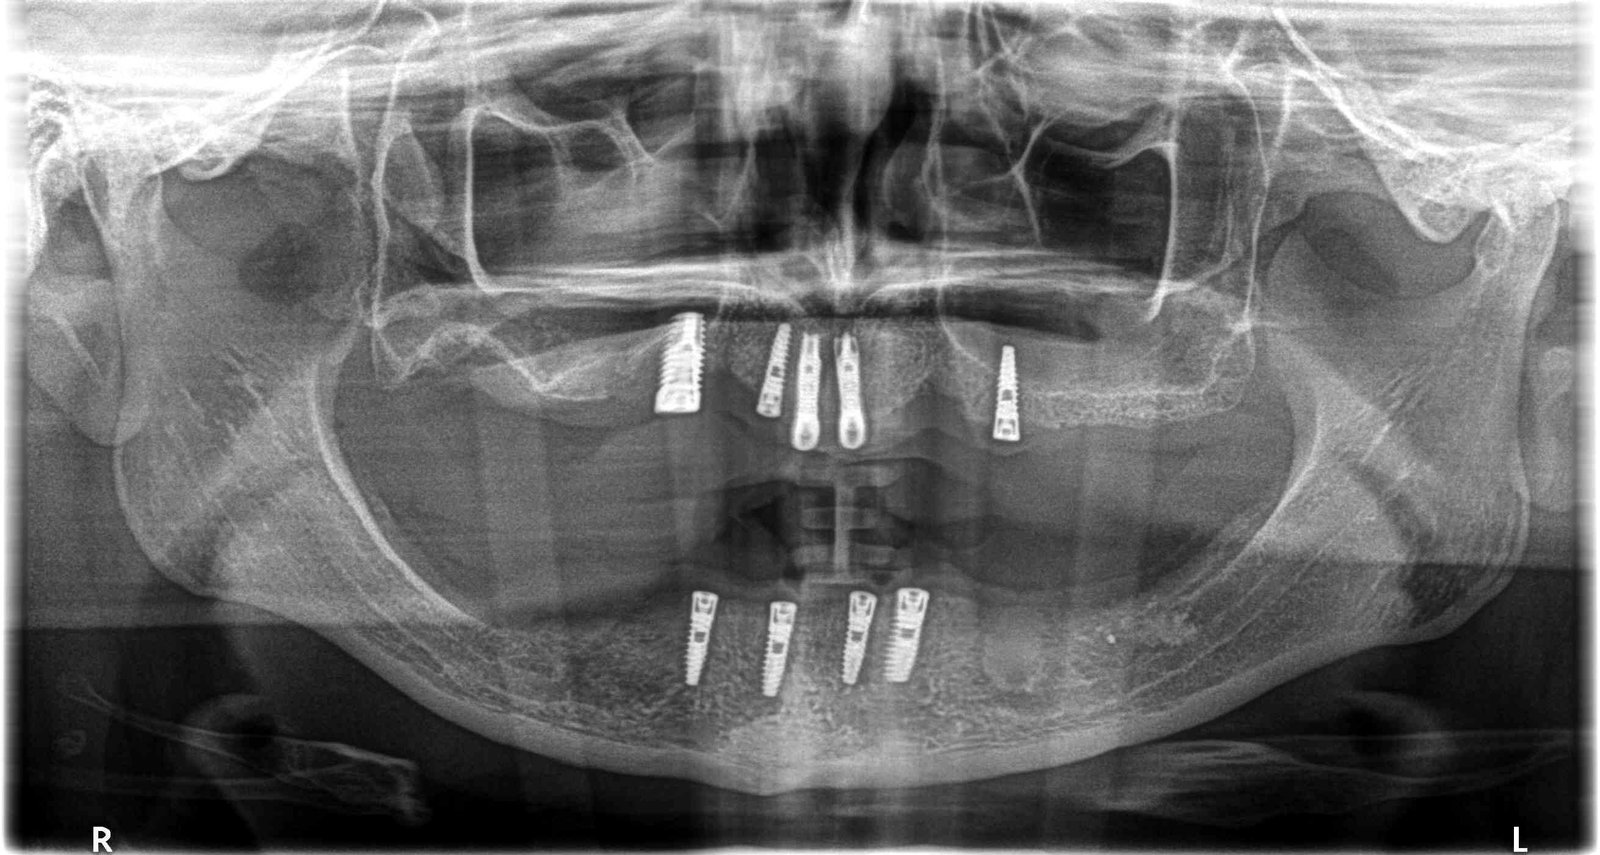

Paciente lleva estos implantes hace más de 10 años y no tiene ninguna referencia. Cree que son Xive. Si nos podéis ayudar, por favor!

¿Nos podrías mandar una periapical lo más paralela y nítida posible? En la pano no se ve nada y la foto del aditamento me sugiere dudas.

Buenas tardes, os adjunto la radiografía periapical.

Gracias por la periapical! Los compañeros comentan que es un 3i Certain prevail de plataforma 4 (azul). Destornillador hexagonal 1.25.

Estoy con el Dr. Antonaya con la identificación.

Lo único, comentar que el destornillador si es hexagonal 1.2 mm.